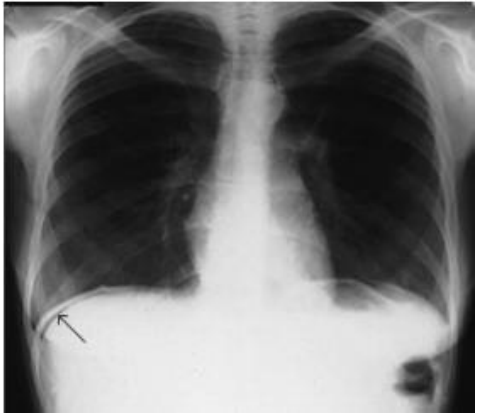

Em relação ao RX para avaliação de pneumoperitônio (vide imagem abaixo), qual é a melhor incidência?

Radiografia do tórax em posição ortostática demonstrando pequeno pneumoperitônio (seta).